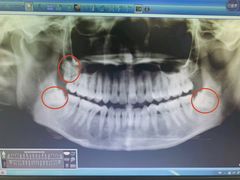

• 深圳市人民医院(留医部)

• -深圳市人民医院(留医部)